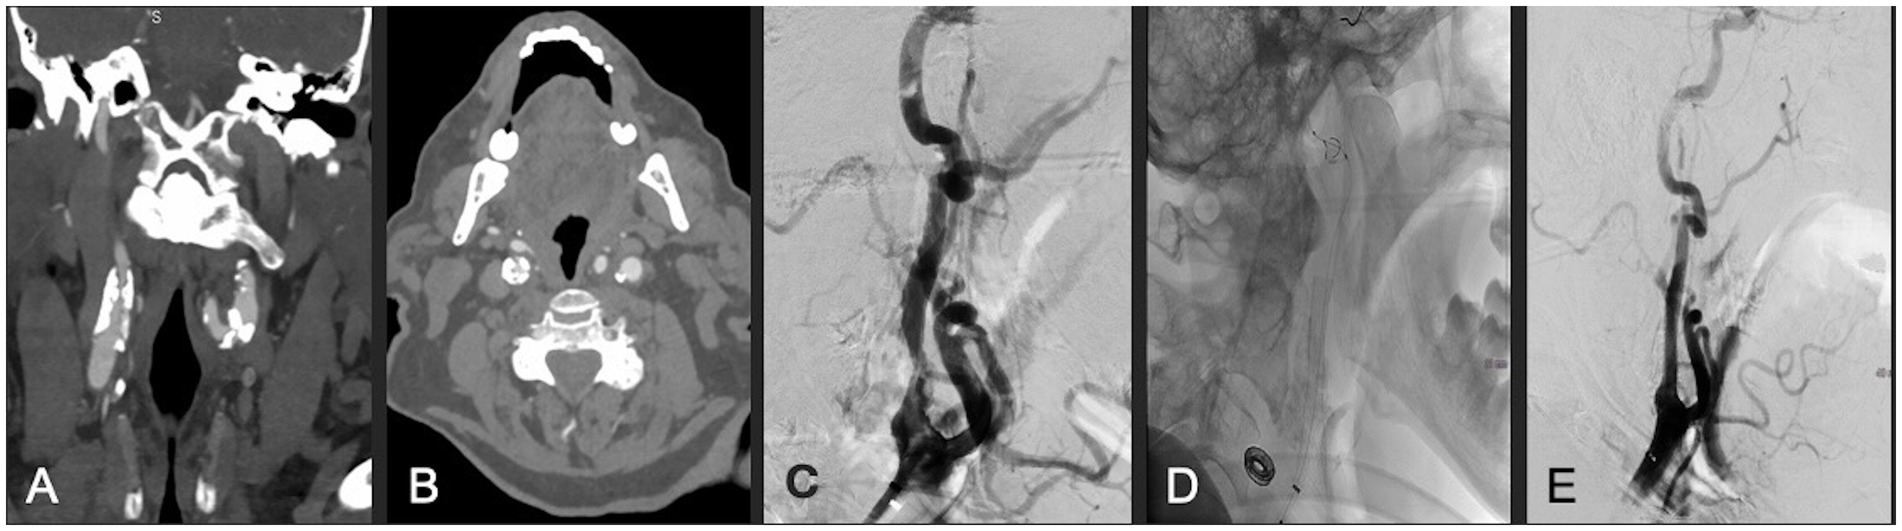

Figure 2. (A,B) Coronal and axial CTA demonstrating right ICA circumferential calcified stenosis. Catheter angiography demonstrating (C) severe ICA stenosis, (D) carotid stent and distal embolic protection device in place, and (E) significantly improved caliber and flow within right ICA following lithotripsy, stent and angioplasty.

A patient in their 80s presented with progressive confusion as well as blurriness in the left visual field. They were found to have 90% stenosis of the right ICA with a fetal origin posterior communicating artery, arising from anterior circulation, with an associated right occipital infarct. CTA demonstrated extensive calcification of the right carotid bulb, and a very distally located bifurcation that was deemed not amenable to surgery. Therefore, the patient was successfully treated with IVL and stenting via one episode of sonic pulses (Figure 2). Post-angiogram ultrasound findings showed PSV of 100 cm/s, a peak systolic ICA/CCA velocity ratio of 1.2, and less than 50% stenosis in the right ICA. The patient had a 7-day hospital stay without post-procedural complications, after which they were discharged to a rehabilitation hospital. At 1-month follow-up, the patient’s confusion had resolved; however, a left inferior homonymous quadrantanopia persisted. Unfortunately, the patient was diagnosed with lung cancer and died 19 months following the procedure secondary to acute hypoxic respiratory failure.